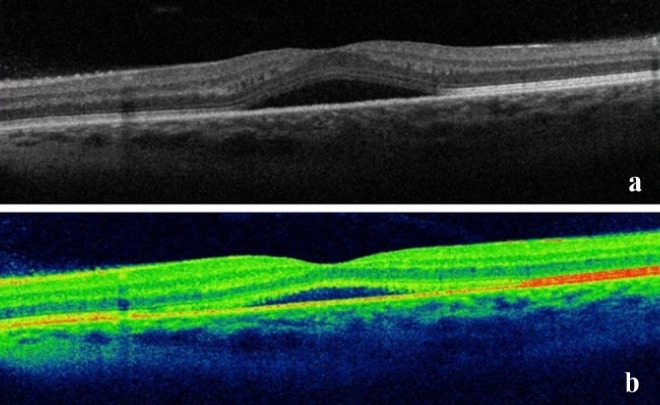

Case description: We present a case of a metastatic breast cancer patient with central serous chorioretinopathy, recurrent cystoid macular edema, and radiation-induced optic neuropathy that occurred after the treatment with paclitaxel and radiation. A 42-year-old female patient presented to our department with a one-week history of painless, subacute vision loss in her left eye, occurring one year after completing oncological treatment. Her best corrected visual acuity (BCVA) was 20/32 in her left eye, and the optical coherence tomography (OCT) showed central serous chorioretinopathy with spontaneous resolution within 1 month. Seven months later, she presented with a sudden decrease in vision in her right eye; the BCVA was 20/40, the relative afferent pupillary defect was found, and the visual field demonstrated a superior altitudinal defect corresponding to the inferior segmental optic nerve pallor, prompting us to start treatment with prednisolone. Six months later, her vision had fallen to light perception in the right eye and 20/25 in the left eye. The OCT findings were conclusive for cystoid macular edema in her left eye, so we started treatment with aflibercept. Unfortunately, we could not improve the visual outcome in the right eye, which had an amaurotic pupil. Regarding the left eye, the patient experienced recurrent macular edema treated with aflibercept. After several episodes, the patient's BCVA decreased to 20/50 without any improvement.